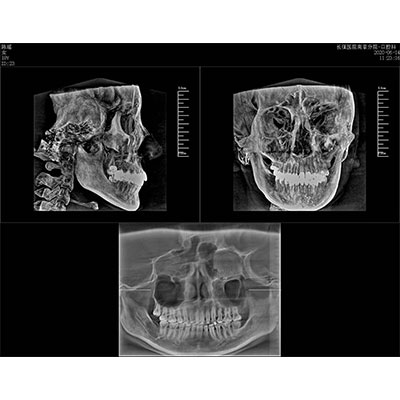

該款牙科CBCT產(chǎn)品采用動(dòng)態(tài)平板探測(cè)器,獲得三維圖像的同時(shí)還具有數(shù)字化全景功能,廣泛應(yīng)用于口腔頜面外科、正畸科、正頜外科、種植科、牙體科、顳下頜關(guān)節(jié)科等術(shù)前術(shù)后。

專有三維重建算法,可提供任意位置高清斷層影像。

可同時(shí)觀察軸向面、冠狀面和矢狀面圖像,方便臨床診斷。